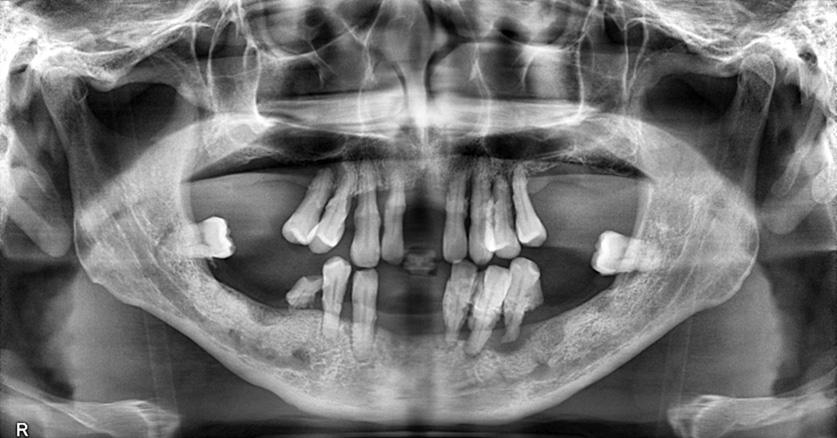

術前のパノラマX線写真

下の前歯3本が自然脱落されたとのことでした。下の入れ歯はご使用ではなかったため、入れ歯修理で対応することはできませんでした。入れ歯を一から製作する必要があり、かつ見た目や発音の点から、早急な対応をご希望でした。3日連続で来院していただけたため、早急に入れ歯を装着することができました。